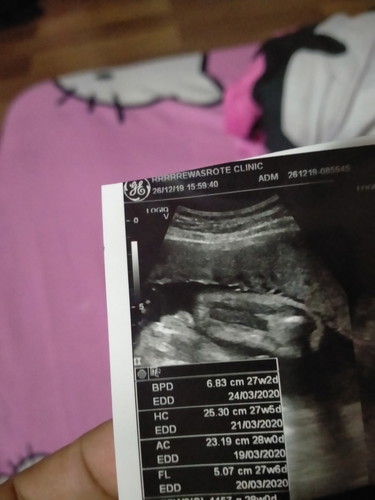

28w พึ่งไปซาวมาวันนี้คุณหมอบอก มีกลีบ2กลีบนะคุณแม่ ได้ลูกสาวชัวร์